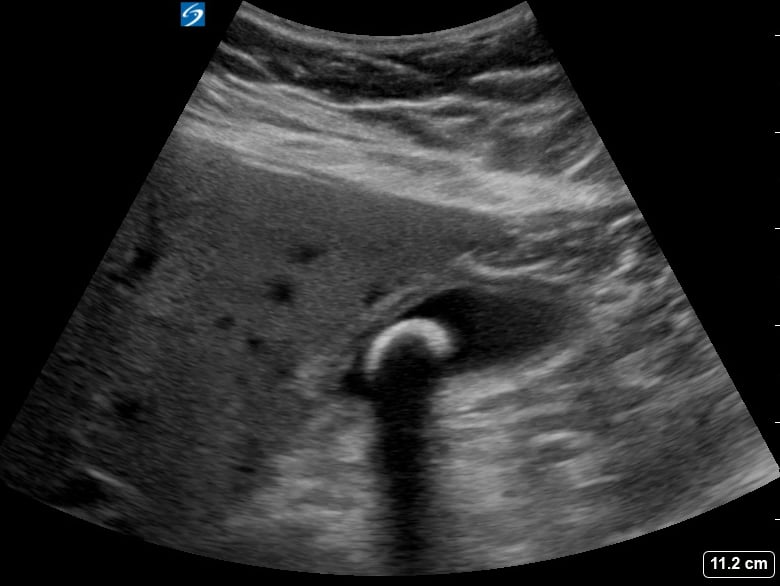

Pericholecystic fluid, in abdominal ultrasound, refers to an abnormal collection of fluid surrounding the gallbladder. Its presence is a key indicator of gallbladder inflammation, commonly seen in acute cholecystitis, a condition causing severe abdominal pain. Sonographers meticulously assess this fluid for its location, amount, and characteristics to aid in accurate diagnosis.

This fluid accumulation is a crucial diagnostic sign for healthcare professionals. Early detection via ultrasound helps guide timely medical intervention and treatment strategies, preventing further complications related to gallbladder disease and improving patient outcomes in abdominal imaging.